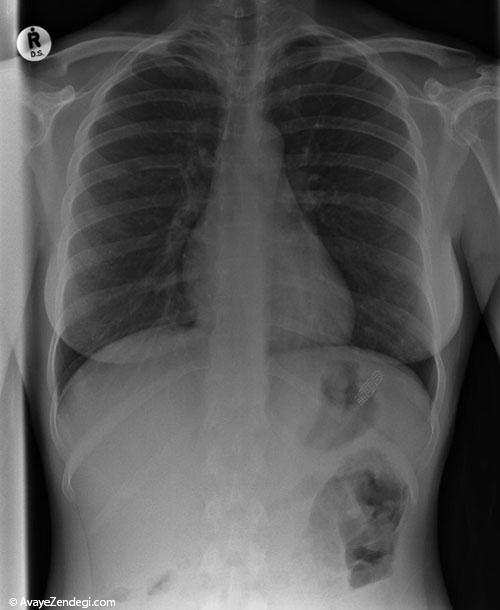

۱- لو یانگ 31 ساله در ناچانگ چین که به رغم اصابت چاقو به قلبش، جان سالم به در برد.

۳- این عکس اشعه ایکس از قفسه سینه، ارهای دندانهدار (اره برقی سبک) را نشان میدهد که در گردن و شانههای والتاین فرو رفته است. والتاین ۲۱ ساله مشغول هرس درختان بود که ناگهان اره او به او برخورد کرد و تیغههایش در بدن او فرو رفت. همکارانش او را از بالای درخت پایین آوردند و به بیمارستانی در پیتزبورگ پنسیلوانیا انتقال دادند.